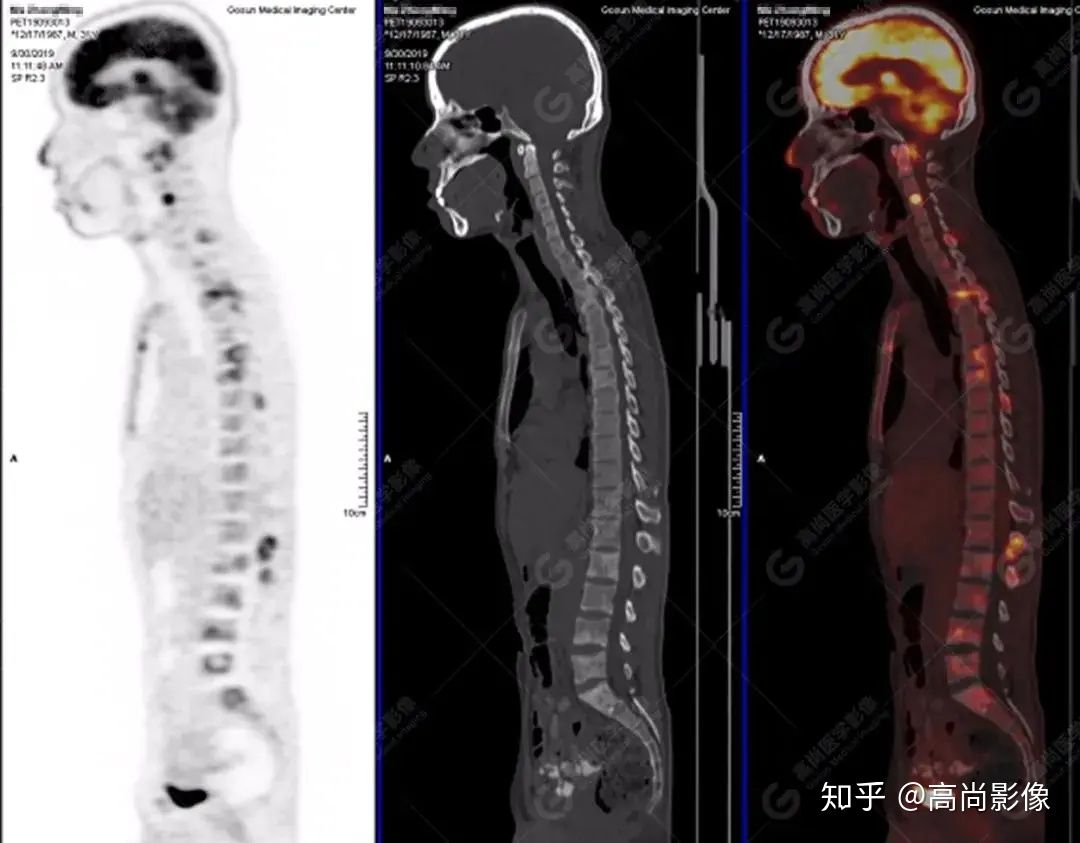

PET/CT 全身圖

脊柱多發(fā)椎體及附件骨質(zhì)破壞,代謝不均性增高